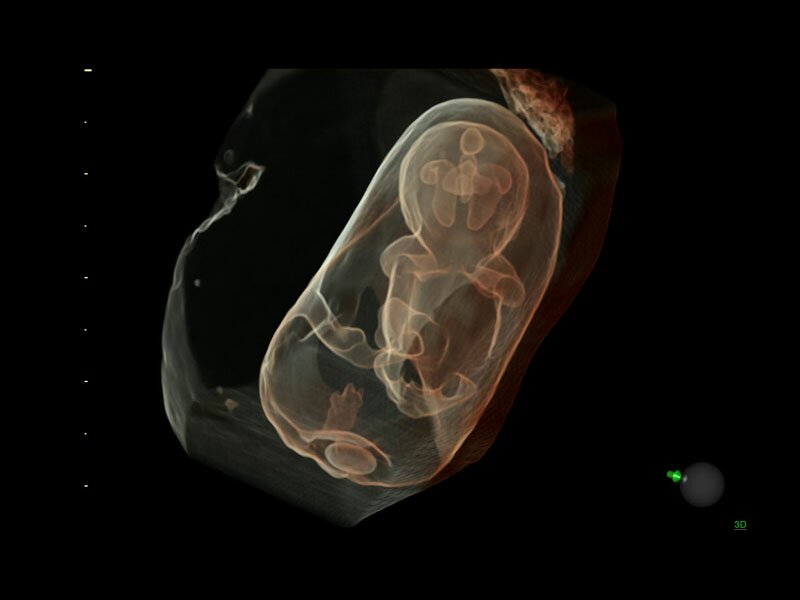

• Программа объемной визуализации плода классический HD-Live + расширенный пакет Hdlive Silhouette и Studio:

• HDlive Flow - перемещаемый источник света, совместимый с визуализацией кровотока в 3D

• HDlive Silhouette - режим "Силуэт" с подчеркиванием границ тканей и объектов, "объем в объеме"

• HDlive Flow Silhouette - режим "Силуэт" с выделением границ полостей сердца и сосудов, совместимый с визуализацией кровотока

• HDlive Studio - три независимых источника освещения с регулировкой интенсивности

Объемное сканирование Voluson — 3D/4D вашей мечты

Объемное УЗИ на Voluson E10 — это не просто потрясающе красивая картинка, это ценный инструмент получения дополнительной информации при обследовании женщин.

Voluson E10 поддерживает инновационные технологии формирования изображений — HDlive Silhouette и HDlive Flow, которые позволяют увидеть мельчайшие детали. Алгоритм SonoRenderlive упрощает рабочий процесс и дает возможность реконструировать изображение поверхностей, определяя область перехода между тканью и жидкостью.

Инновационная технология визуализации HDlive обеспечивает получение реалистических изображений за счет эффекта объемного зрения, повышая достоверность клинической оценки. Теперь режим HDlive дополняют две новые функции:

• Технология HDlive Silhouette — задает разный уровень прозрачности, помогая выявлять контуры внутренних структур и точнее оценивать состояние плода в первом триместре.

• Технология HDlive Flow — повышает реалистичность визуализации сосудистых структур, улучшая восприятие глубины (по сравнению с традиционным цветовым допплером и функцией HD-Flow).